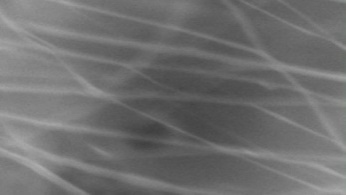

Morphology, size and size distribution of the nanofibres

Morphology analysis was adapted from Aytac et al. (2019) [38]. The SEM analysis was conducted to detect electrospun nanofibers' fibre shape and diameter. The electrospun nanofibres from 18 runs were investigated individually by SEM (FEI, quanta 450, Czech). Images revealed the morphology of resultant nanofibers and measured their diameters in nanometres. The average number of records was calculated using a standard deviation estimation. The setting of the SEM machine was conducted on voltage 25.00 kv, magnification 23624 and width (8.3-9.3 mm).

Results of the SEM analysis are listed in table 2, with a wide range of fibre diameters starting from 87.2 nm (run 13) to 2500 nm (run 18). Run 18 did not produce true nanofibers due to the deficient concentration of PVA. The statistical analysis revealed that the effect of each polymer (factor) on the diameter size of the electrospun nanofiber was vast. Therefore, there is a correlation between factors A, B and C and fibre diameter as expressed in equation 5.

Fig. 3: Nanofibres SEM images with nanofiber diameter frequencies. The PVA, PEO and HPMC were symbolised as V, E and P. Data are given in mean±SD, n=3

The morphology of nanofibers would be affected by device parameters such as flow rate, voltage and distance from the collector. Also, nanofibres' properties could be changed due to temperature and humidity. The bead formation appears with a low concentration of PVA (run 2) or a high concentration of PEO and HPMC (runs 6 and 11), as shown in fig. 3. Therefore, increasing PVA concentration leads to beads' disappearance and smooth fibres' formation. Nageeb El-Helaly (2021) and Silva J. A. et al. (2021) reported similar results [47, 48]. Kalluriet al.(2021)[49] studied the relationship between the fibre diameter, bead diameter and flow rate. Thus, they concluded that better fibre uniformity and bead formation were needed at a high flow rate. These results appear clearly in run two and run six and agree with Silva et al.(2021) results [50], who reported that only the concentration of PVA (≥ 15%) could produce uniform nanofibers when using the lower molecular weight of PVA (67,000). Fibre diameter of 15% PVA and more appeared to be in the range 87.11 to 252.5 nm with uniform fibres and disappearance of beads except in run 6, where the beads appear due to increasing the concentration of HPMC as highlighted by Gripet al. (2018) [46].